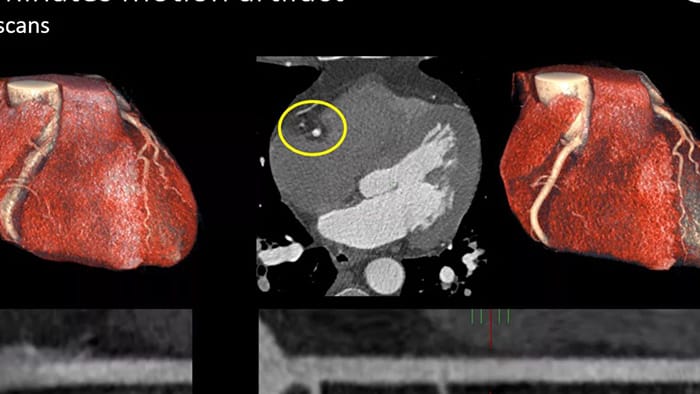

Op ESC 2024 presenteert Philips nieuwe echocardiografie toepassingen waarin gebruik wordt gemaakt van nog niet eerder beschikbare AI-toepassingen die helpen echocardiografiemetingen te versnellen en te automatiseren. Het nieuwe geavanceerde platform beschikt over innovatieve AI-tools die zijn ontworpen om de diagnose van structural heart diseases (SHD) te ondersteunen, waaronder een nieuwe geautomatiseerde 3D-tool voor tricuspidalisklepkwantificering [1] en nieuwe 3D-kleurstroomkwantificering om te helpen bij het diagnosticeren van mitralisinsufficiëntie.

Op de ESC 2024 wordt ook het nieuwste AI-gestuurde cardiovasculaire echografieplatform van Philips geïntroduceerd. Dit platform is het eerste in de sector met toepassingen die zijn ontworpen om met behulp van bewezen technologie de analyse van echocardiografische resultaten te versnellen. Dit platform is nu geïntegreerd met Philips Ultrasound Workspace en maakt hetzelfde mogelijk. Het ondersteunt consistente diagnostische mogelijkheden waardoor geavanceerde analyses van leveranciersonafhankelijke gegevens mogelijk zijn om de besluitvorming in het hele cardiologische zorgpad te verbeteren.